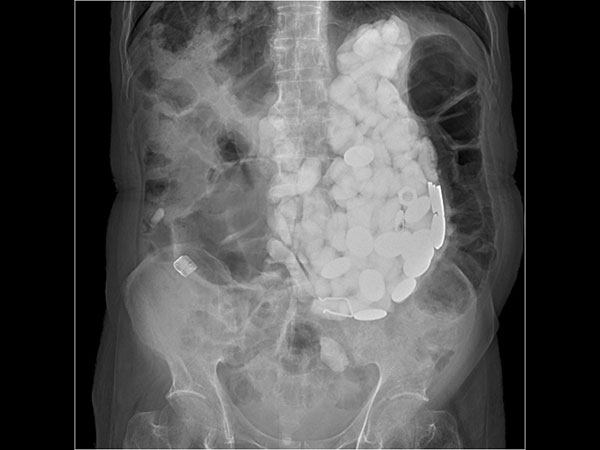

രണ്ട് കിലോയിലധികം വസ്തുക്കള്

ഇദ്ദേഹത്തിന്റെ വയറ്റില് ഏകദേശം രണ്ട് കിലോയിലധികം വസ്തുക്കളാണ് കണ്ടെത്തിയത്. ദിവസം ചെല്ലുന്തോറും ഇതെല്ലാം വിഴുങ്ങിയതിന്റെ ഫലമായി അദ്ദേഹത്തിന്റെ ശരീരം ശോഷിച്ച് വന്നു. 9 ദിവസത്തോളം ഇദ്ദേഹം ആശുപത്രിയില് കിടന്നു. ഇപ്പോള് പൂര്ണമായും ഈ പ്രശ്നത്തില് നിന്ന് ഇദ്ദേഹം പുറത്ത് വന്നിട്ടുണ്ട്.